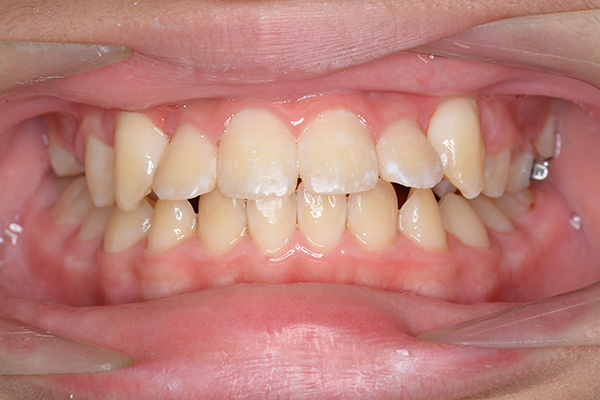

| 批評・予后 | 埋伏歯の牽引を行い位置異常の改善をした結果、適切な犬歯のガイドが得られ、ほぼ緊密な咬合となったように思う。口元の改善を希望された場合は小臼歯抜歯症例として本格矯正治療を行う予定である。 |